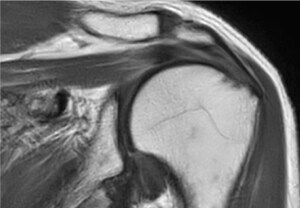

Me asombra el gran potencial de Smart Speed. Ahora es posible obtener imágenes musculoesqueléticas en 3D. Gracias a ello, obtengo imágenes de muy buena calidad en un tiempo de exploración muy corto, lo que es fundamental en un centro de diagnóstico por imagen privado como el nuestro.”

Dr. Tobias Schröter

MRT-Praxis Postdam, Alemania